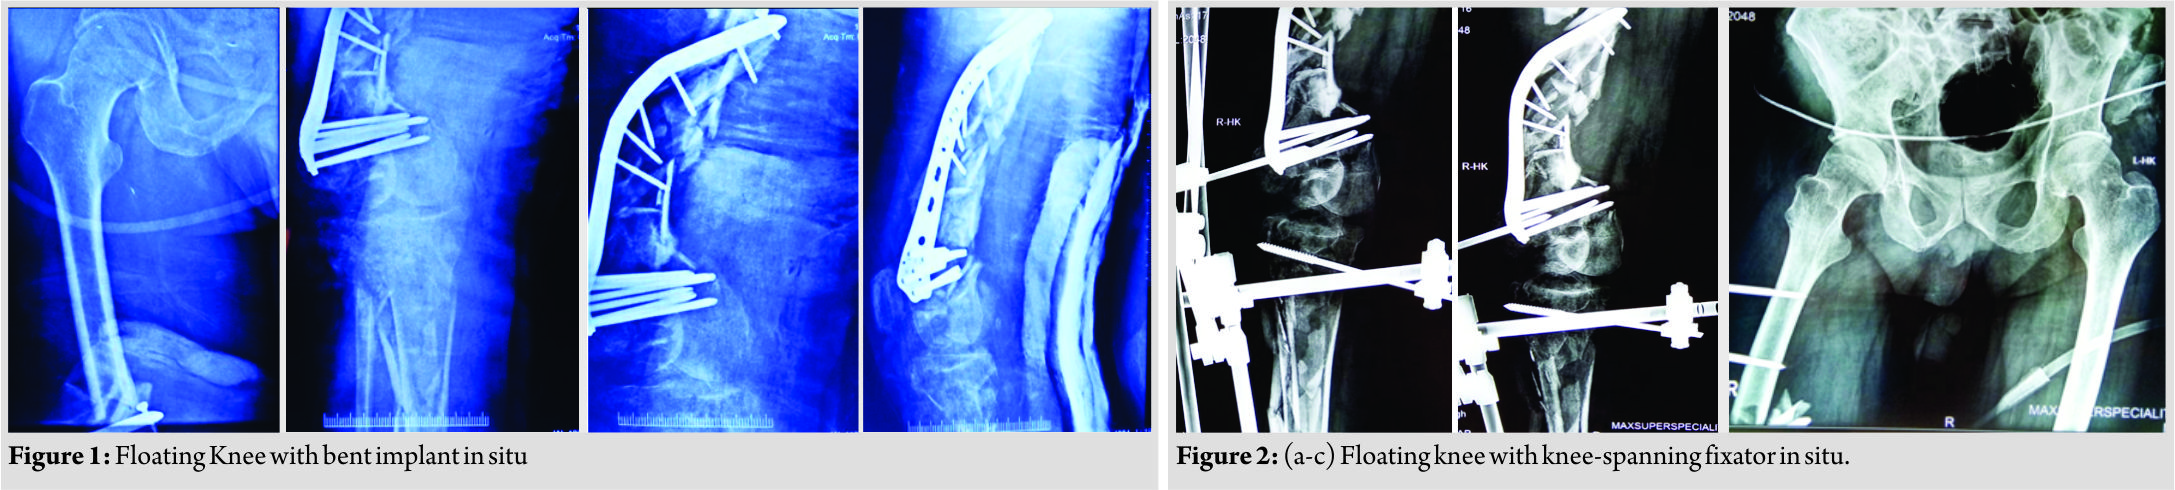

A 56-year-old diabetic, hypertensive man on antipsychotic medications who jumped from about 30 feet height, sustained polytrauma and was admitted in a local hospital. After initial resuscitation and advanced trauma life support (ATLS) care, he was intubated and put on ventilator support. He was diagnosed with bilateral hemothorax and his right lower limb X-rays showed fracture lower one-third femur with extensive metadiaphyseal comminution and fracture ipsilateral proximal tibia extending to metaphysis. A locking distal femoral locking plate was present and had bent (Fig. 1). As per records, he had 3*2 cm wound on anterior aspect of thigh which was thoroughly washed, debrided, and sutured and damage control [7]surgery was done in the form of knee-spanning fixator (Fig. 2) and the patient was put on intravenous antibiotics. He stayed in the intensive care unit (ICU) for 7 days, after which he was shifted to our center. As a part of repeat evaluation, all his necessary X-rays were retaken (Fig. 3) which revealed resolution happening in bilateral hemothorax. The right lower limb X-rays revealed knee-spanning external fixator with fracture of lower end femur and proximal end tibia with bent implant in situ (Fig. 2). The patient was kept in the ICU till he was fit for subsequent intervention and appropriate treatment in the form of intravenous antibiotics and deep vein thrombosis prophylaxis was given. During this period, the patient had low-grade fever, but his inflammatory markers were normal and the wound over the thigh was healthy. On the 8th day, he was taken up in the operation theater with intubation on. Before removing external fixator, the wound present on anterior aspect of distal thigh was again debrided and found to be clean; then, the decision to proceed further was made and the external fixator was removed. The distal femur was opened through lateral approach using liberal skin incision (Fig. 4).

The patient was kept in the ICU till he was fit for subsequent intervention and appropriate treatment in the form of intravenous antibiotics and deep vein thrombosis prophylaxis was given. During this period, the patient had low-grade fever, but his inflammatory markers were normal and the wound over the thigh was healthy. On the 8th day, he was taken up in the operation theater with intubation on. Before removing external fixator, the wound present on anterior aspect of distal thigh was again debrided and found to be clean; then, the decision to proceed further was made and the external fixator was removed. The distal femur was opened through lateral approach using liberal skin incision (Fig. 4). After splitting the distal part of tensor fasciae latae, the distal locking screws were removed.Since the plate was bent, a bone hook was used to pull out the proximal end of plate laterally. Now, the position of the proximal screws was marked under C-arm control using an artery forceps. Each screw head was cleared causing minimal muscle damage and they were removed in a minimally invasive fashion, thus preserving the biology of zone of comminution and the plate was gently levered out. Following implant removal, we identified that there was another fracture line in coronal plane just posterior to plate application in the articular block which was identified as lateral condyle Hoffa fracture. The articular reconstruction was first done and the Hoffa fracture was fixed using single partially threaded cancellous screw. Manual linear traction was applied to the limb after reconstructing articular block and grossly comminuted fragments were seen to be aligned, so no attempt was made to open the comminuted area. The length of the limb was maintained by giving linear traction and an electrocautery was used to ensure that the center of femoral head, patella, and second toe lie in same line and checked under C-arm to maintain the correct rotation of the limb. The longest available distal femur locking plate (A.O SYNTHES) in the set was slid in a MIPPO fashion bypassing the zone of comminution after reconstructing the articular block. Same incision was extended below knee to expose proximal tibia and the longest available lateral tibia locking plate(A.O SYNTHES) was slid in a MIPPO manner bypassing the comminution. Now, after fixing both the fractures, the knee was examined for ligamentous instability and it was found to be globally unstable in both the planes. Considering the gross comminution in both femur and the tibia, and the being an open fracture, it was decided to wait for ligamentous reconstruction till bony union was achieved. Wound was sutured in layers over negative drain and a long knee brace was given to the patient since the knee was unstable in both the planes.The patient was shifted out of theater in an intubated state. Immediate post-operative X-rays revealed satisfactory alignment of both fractures, (Fig. 5). During the next 7 days, the patient remained intubated and during this period, the passive movement of joints was given, the limb was elevated and the stitch line was carefully monitored. Once the patient was extubated on the 8th day, it was found that there was an associated foot drop which was missed preoperatively since the patient was in an intubated state. The foot drop splint was applied accordingly and physiotherapy in the form of guarded ROM and muscle strengthening exercises was started. We could not ambulate the patient as he had another fracture in the wrist in the recent past, (Fig. 6).

After splitting the distal part of tensor fasciae latae, the distal locking screws were removed.Since the plate was bent, a bone hook was used to pull out the proximal end of plate laterally. Now, the position of the proximal screws was marked under C-arm control using an artery forceps. Each screw head was cleared causing minimal muscle damage and they were removed in a minimally invasive fashion, thus preserving the biology of zone of comminution and the plate was gently levered out. Following implant removal, we identified that there was another fracture line in coronal plane just posterior to plate application in the articular block which was identified as lateral condyle Hoffa fracture. The articular reconstruction was first done and the Hoffa fracture was fixed using single partially threaded cancellous screw. Manual linear traction was applied to the limb after reconstructing articular block and grossly comminuted fragments were seen to be aligned, so no attempt was made to open the comminuted area. The length of the limb was maintained by giving linear traction and an electrocautery was used to ensure that the center of femoral head, patella, and second toe lie in same line and checked under C-arm to maintain the correct rotation of the limb. The longest available distal femur locking plate (A.O SYNTHES) in the set was slid in a MIPPO fashion bypassing the zone of comminution after reconstructing the articular block. Same incision was extended below knee to expose proximal tibia and the longest available lateral tibia locking plate(A.O SYNTHES) was slid in a MIPPO manner bypassing the comminution. Now, after fixing both the fractures, the knee was examined for ligamentous instability and it was found to be globally unstable in both the planes. Considering the gross comminution in both femur and the tibia, and the being an open fracture, it was decided to wait for ligamentous reconstruction till bony union was achieved. Wound was sutured in layers over negative drain and a long knee brace was given to the patient since the knee was unstable in both the planes.The patient was shifted out of theater in an intubated state. Immediate post-operative X-rays revealed satisfactory alignment of both fractures, (Fig. 5). During the next 7 days, the patient remained intubated and during this period, the passive movement of joints was given, the limb was elevated and the stitch line was carefully monitored. Once the patient was extubated on the 8th day, it was found that there was an associated foot drop which was missed preoperatively since the patient was in an intubated state. The foot drop splint was applied accordingly and physiotherapy in the form of guarded ROM and muscle strengthening exercises was started. We could not ambulate the patient as he had another fracture in the wrist in the recent past, (Fig. 6). The wound healing was bit delayed but it was ultimately uneventful. An X-ray was taken at 6 weeks post-operative which revealed satisfactory alignment (Fig. 7) and toe touch weight-bearing with long knee brace was started under supervision of trained physiotherapists. The patient was further followed up at 1 month interval and during this rehabilitation period, special attention was given to his psychiatric care. At the latest follow-up of 6 months, the patient had radiological and clinical evidence of union (Fig. 8). At the last available follow-up,the ligamentous instability still persisted, and with long knee brace, he was able to stand and walk. The foot drop was also recovering and there was no extension lag and knee flexion was upto 90° (Fig. 9). At this moment, he was properly counseled and explained in detail about all the available options in the form of arthrodesis, hinged knee arthroplasty, and ligamentous reconstruction, but the patient opted for non-operative management in the form of long knee brace for the time being.

Floating knee is the term used when the knee is partially or completely isolated from the rest of the extremity due to the fracture of femur and tibia. These are often associated with injuries to chest, abdomen, or head [1]. Floating knee was first classified by Fraser et al. [4]. Type 1 is the true floating knee in which neither the femoral nor the tibial fracture extends to the knee. Type 2 is a variant in which one or both the fractures involve the knee. Type 2 is further classified according to the knee injury. Type 2 a is a tibial plateau fracture associated with femoral shaft fracture while Type 2b is an articular fracture of distal femur associated with tibial shaft fracture and Type 2c is a fracture of tibial plateau and articular fracture of distal femur [8]. The present case had comminuted fracture of femur involving the articular area with comminuted fracture of proximal tibia with articular involvement. In this classification, there is no mention of any comminution of metadiaphyseal in any of the group so the nearest fracture type under which our fracture can be classified is 2c. The presence of the previous implant had further complicated the injury pattern. In addition, there was associated lateral condyle Hoffa fracture which was missed preoperatively because attention was given to more significant injuries and was seen intraoperatively after removing the previous bent implant. The floating knee is often a part of polytrauma situation and so the patients can be hemodynamically unstable, and therefore, particular attention has to be given to life-threatening injuries and ATLS protocols must be followed [9]. Floating knee is much more than a bony entity alone. Death rate on admission can be as high as 10% [10,11,12]. The present case had been accordingly given care at the index hospital and was kept in the ICU. The first intervention in majority of these patients is in the form of damage control orthopedics. In this approach, minimal intervention is done to stabilize fractures especially of long bones and this minimizes the second hit phenomenon [13]. In our case, damage control was done at the index hospital in the form of knee-spanning external fixator. Popliteal artery lesions can be seen in 7% of cases and it is often an open injury and rate as high as 69% has been reported [8]; compartment syndrome has also been reported [14]. The present case also had an open Grade 2 injury and also had neurological involvement in the form of common peroneal nerve injury which was missed preoperatively since the patient was in an intubated state and was realized only when he was extubated. Paul et al. reported 21 patients with fractures of ipsilateral femur and tibia and found that more than 50% of patients suffered ipsilateral knee injuries [2]. Szalay et al. examined 110 Australian patients with 114 femoral shaft fractures and reported ligament laxity in 27% of patients. In addition, they investigated other 33 patients with 34 ipsilateral femoral and tibial fractures. In this group, 53% of patients had knee ligament laxity, leading to the conclusion that knee ligament injury is more common in the simultaneous femoral and tibial fractures than in the single femoral fractures [15]. Pietu et al. reported that of 172 cases of floating knees, 11% had early diagnosed anterior cruciate ligament ruptures, but 15.7% presented with late severe laxity clearly indicating underestimation of associated ligamentous lesions [8]. The repair of ligament injuries can be delayed till the bony fractures have healed, although it is still a matter of debate among many researchers [15, 16]. The present case also had ligamentous injury which was missed preoperatively since the patient had knee-spanning external fixator in situ and it was diagnosed on table after fixing both femoral as well as tibial fractures. However, considering the gross comminution and open nature of the injury, it was decided to wait for ligamentous reconstruction till solid bony union was achieved. This was given as an option to the patient at follow-up, but he opted for conservative management in the form of long knee brace. The definitive treatment of floating knee involves surgical stabilization of both the fractures. The choice of implant, the sequence of fixation, and the surgical approach depend on numerous factors such as patients general physical condition, associated comorbidities, soft tissue injury, available resources, and last surgical proficiency. Intramedullary nailing appears to be the gold standard for Type 1 injuries which are diaphyseal while in Type 2 injuries, anatomical reconstruction of the joint takes priority and after doing so, metaphyseal-diaphyseal comminution can be stabilized in aminimally invasive fashion using locking plates [17, 18]. Rios et al. studied 43 patients with floating knee injuries and in a subgroup of 25 patients, they performed retrograde femoral nailing and antegrade tibia nailing through single incision and in another subset of 18 patients, they used traditional antegrade femoral nailing and tibia nailing. They concluded that single incision technique is an excellent option for Type 1 floating knee injuries [19]. In another study by Kao et al. [20], femoral fractures around trochanteric area were fixed using various implants in the form of cannulated screws, dynamic hipscrews, and dynamic compression screws, whereas femoral shaft fractures were fixed using intramedullary nailing either in supine position or using traction table.Tibial fractures around tibial plateau, proximal tibia, or distal tibia were fixed using compression plates or interlocking nailing depending on the fracture location. Theodratus et al. recommended intramedullary nailing as the best treatment choice except for Grade 3b and 3c open fractures [21]. The evidence for the indications and special technical considerations of the plating in floating knee injuries is sparse. Ran et al. [22] reported on outcome and management of 28 patients with floating knee injuries. In 14 cases, simultaneous plating of distal femur and proximal tibia was done. The results of plating of both fractures were excellent in 1, good in 7, acceptable in 3, and poor in 3 according to the Karlstrom and Olerud classification. In our case, considering the intra-articular nature of both distal femur and proximal tibia fractures along with the extensive metadiaphyseal comminution, the only suitable option available was plating of both the fractures. In addition, removal of the previous implant was a challenge. Hence, careful retrieval of plate and screws without disturbing the biology of smaller fragments was essential and with that due care, another implant was put. Maintaining the length and rotation of the limb were another issue. The length was maintained by manual linear traction and it was ensured that center of femoral head, patella, and second toe lie in same line by keeping electrocautery and checked under C-arm. We believe that the mechanism of injury in our case was axial force transmission along flexed knee which led to high-energy impact on the knee, leading to such a devastating injury. The presence of previous screws into anterior part of femoral condyle could be the reason for associated Hoffa fracture as shown in Fig. 2. Our case report represents an atypical case of floating knee injury and had Hoffa fracture of lateral femoral condyle along with neurological and ligamentous injury, both of which were missed preoperatively. Summarizing, the floating knee injuries are devastating injuries which produce varied results as the incidence of both systemic and local complications is high. Systemic complications could be fat embolism, renal failure, or chest or head injuries, while local complications could be pain, non-union, delayed union, infection, osteomyelitis, or in extreme conditions need to amputate the limb. Even after extensively searching the available literature, we could not find any reference of Hoffa’s fracture associated with floating knee in a previously present implant, and to the best of our knowledge, our case report is the first one to describe such an unusual pattern of injury.